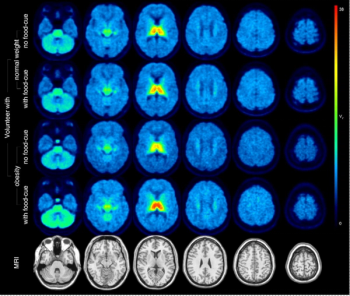

In a study of over 20,700 people, researchers found that artificial intelligence (AI) analysis of body composition measurements via lung cancer screening computed tomography (CT) exams improves the prediction of mortality risks for lung cancer, cardiovascular disease, and all-cause mortality.